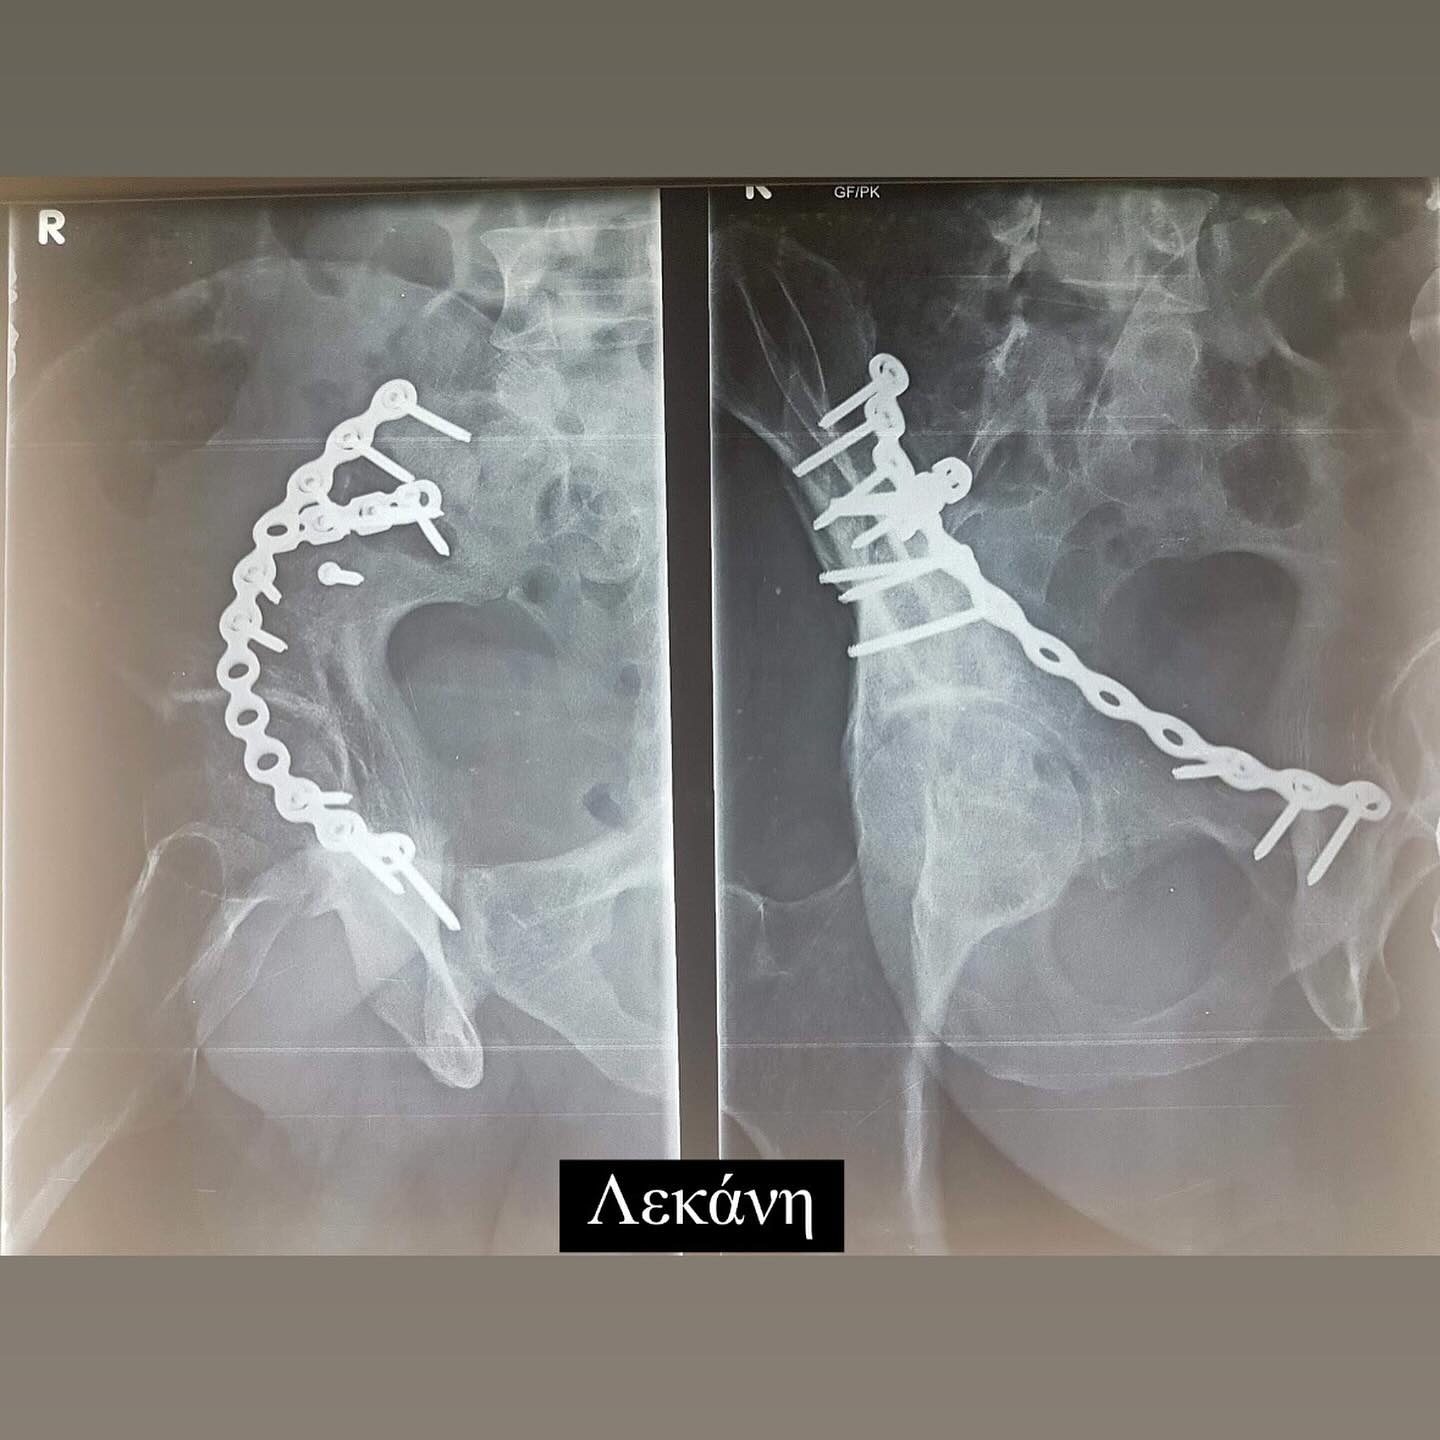

Σήμερα συμπληρώνονται 6 χρόνια από το τροχαίο ατύχημα που είχε ο Ηλίας Βρεττός και δημοσίευσε πρώτη φορά φωτογραφίες από τις ακτινογραφίες που του έκαναν και δείχνουν τα σίδερα που έχει σε χέρι, πόδι και λεκάνη. Συγκεκριμένα έγραψε ο τραγουδιστής: 19/02 Αγία Φιλοθέη μου Μεγάλη η Χάρη σου!!! Σ´ευχαριστώ… 6 χρόνια πέρασαν και όλα ακόμα μοιάζουν σαν χθες… Τα σίδερα μέσα μου που για πρώτη φορα σας δείχνω στα X-rays έτσι κι αλλιώς δεν με αφήνουν να ξεχαστώ. Όμως είμαι καλά και κυρίως είμαι εδώ!